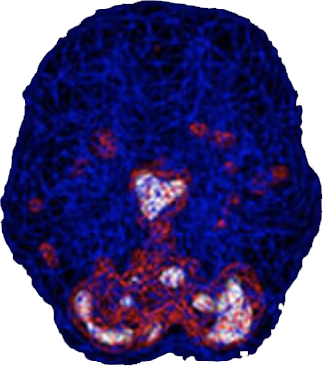

SPECT (single photon emission computed tomography) is a nuclear medicine study that evaluates blood flow and activity in the brain. Basically, it shows three things: healthy activity, too little activity, or too much activity. A healthy “active” scan shows the most active parts of the brain with blue representing the average activity and red (or sometimes red and white) representing the most active parts of the brain. In the healthy scan on the top right, the most active area is in the cerebellum, at the back/bottom part of the brain. In the brain scan below it of a woman with postpartum depression, there is excessive activity in the deep limbic system—the brain’s emotional center.

Healthy Brain Scan

Postpartum Depression

Brain Scan